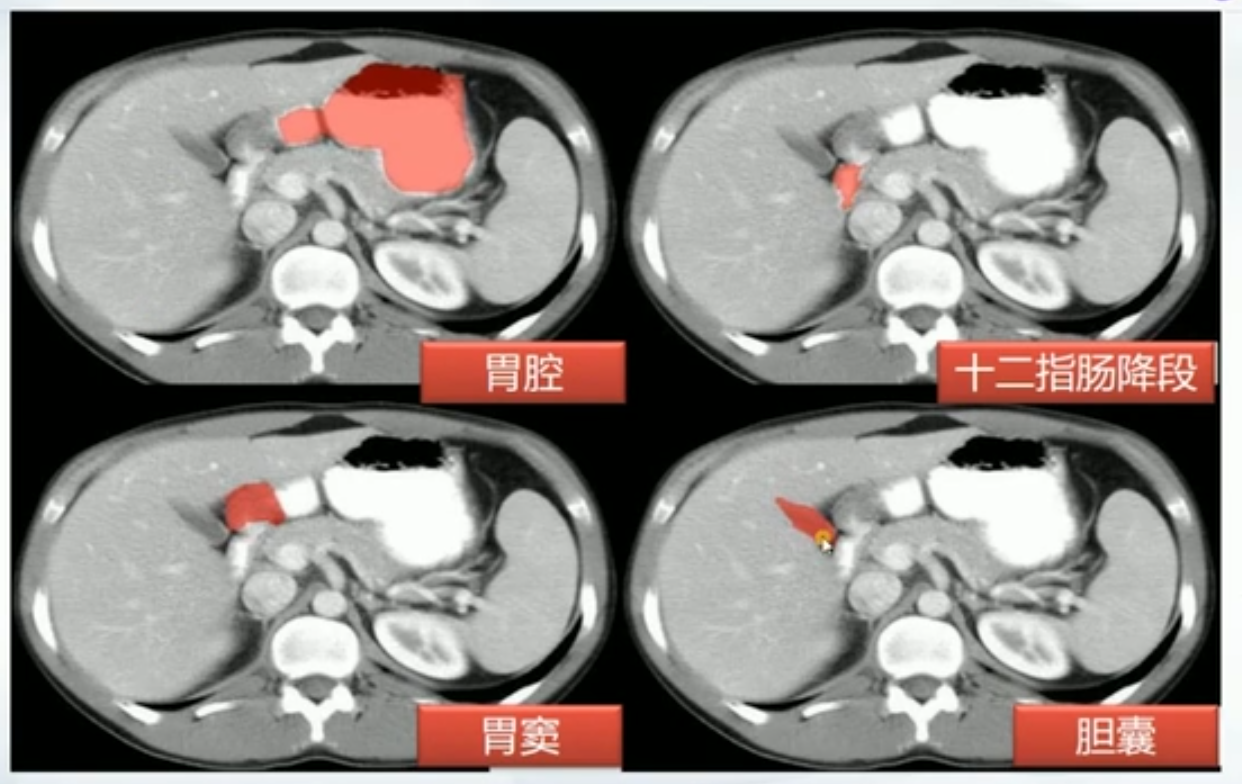

胆总管

- 十二指肠上段

- 十二指肠后段

- 胰腺段:胰腺后方

- 十二指肠壁段:穿入十二指肠内

肝胰壶腹:胆总管十二指肠内开口和胰管汇合形成,周围有Ossid括约肌,控制胆汁和胰液流出,并防止十二指肠内容物反流

- 胆囊结石:正常胆囊里面液体应该和胃内部类似

- 肝门内胆囊里有高密度影

- 胆囊炎:

- 胆囊壁模糊